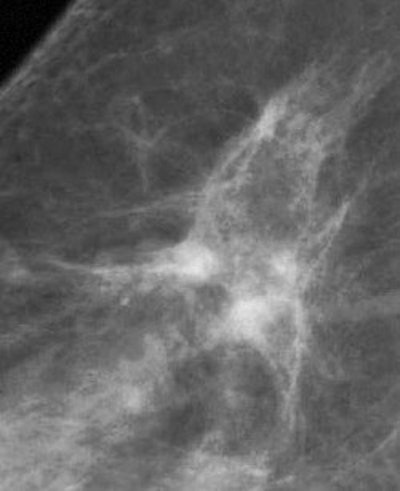

FFDM images acquired on the Senographe 2000D, including zoom (middle) and magnification (below). Images courtesy of Dr. Wolfgang Matzek.